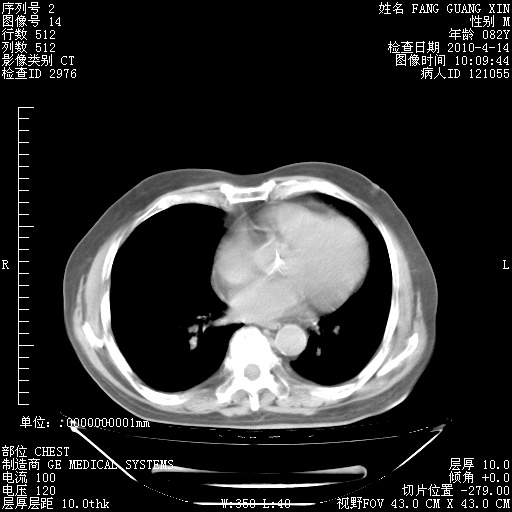

肺部CT平扫未见异常。